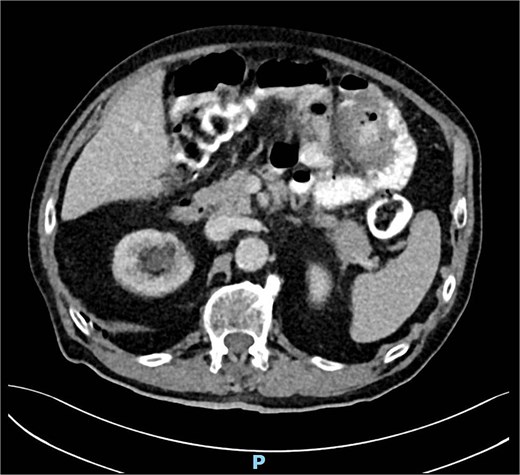

A computed tomography (CT) scan of the abdomen showed an irregularity in the left upper abdomen suspect for a small bowel tumor or inflamed small bowel diverticula (Fig. 3), as well as enlarged mesenteric lymph nodes due to either inflammation or metastasis. Because of the uncertainty of the findings, we decided on an antibiotic treatment and clinical follow up 3 days later.

Intraoperatively, a severe JD was observed. The suspicious area describes in the CT scan was a chronic inflammation due to a diverticulum perforation into the mesentery (Fig. 4). We decided on a segmental resection of ⁓50 cm jejunum leaving only one diverticulum near the ligament of Treitz in situ and a side-to-side anastomosis was performed.

Intraoperative finding of JD with a chronic inflammation matching the findings in the CT scan.